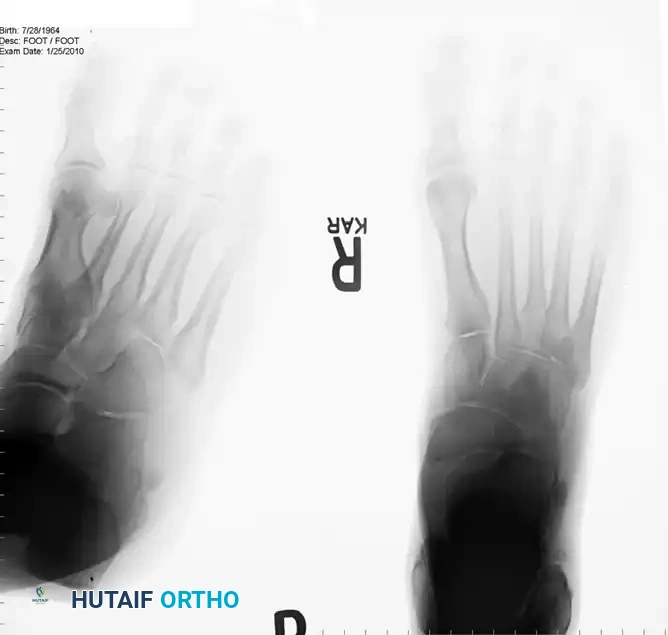

Standard weight-bearing radiographs of the foot and ankle are required to assess for structural malalignment (e.g., varus hindfoot), avulsion fractures of the fibula (fleck sign), and the morphological status of the os peroneum.